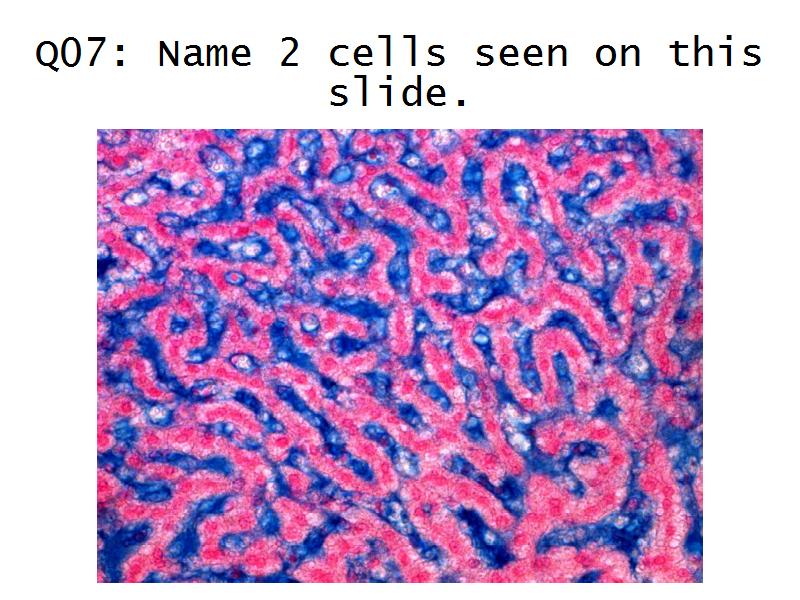

- The renal corpuscle

- Make an annotated diagram of a nephron, including the juxtaglomerular apparatus. Indicate the flow of blood and water in each part, and how solutes are filtered, secreted and reabsorbed.